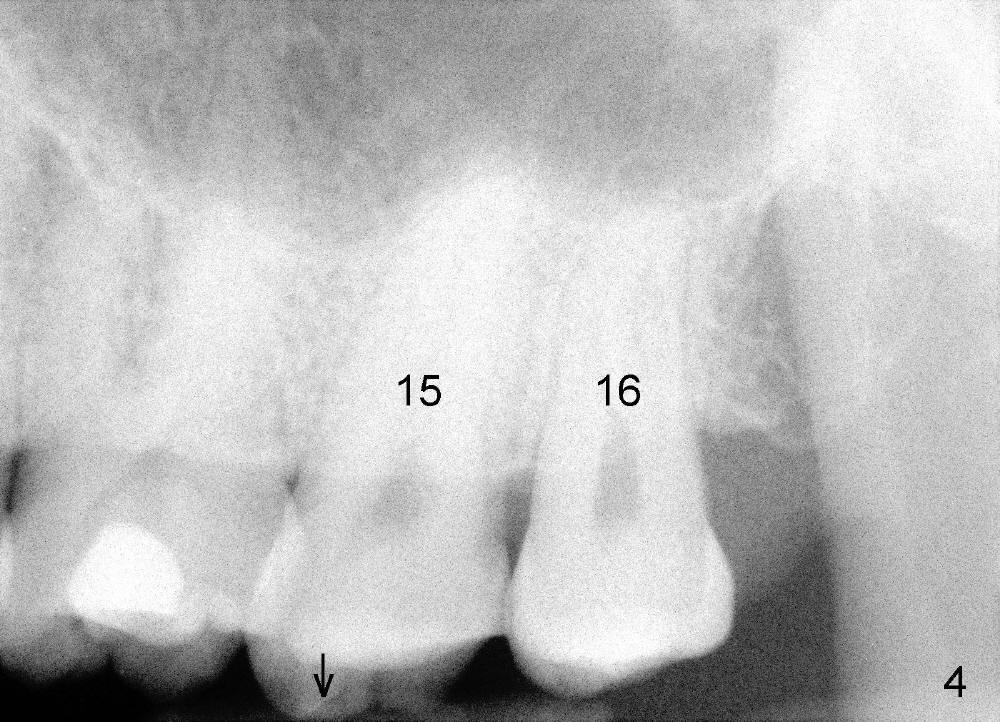

冷先生四五年前来诊所诊治,左下第二磨牙(图一:18)做过根管治疗,牙冠,偶尔不适,近中牙冠不密和(*,open margin),估计迟早会脱落,到时再重做根管治疗(retreat)好像为此不晚,病人听了这个方案没意见。三年半过去了,一切如旧,左下第二磨牙根尖阴影仍存在(图二*),仿佛一个根管没充填(箭头),病人同意拔除左上智齿(图一,四:16)。又过半年左下牙冠终于脱落,病人自动要求重做根管治疗,没充填根管找到,充填(图三箭头),之后症状消失,他很高兴。